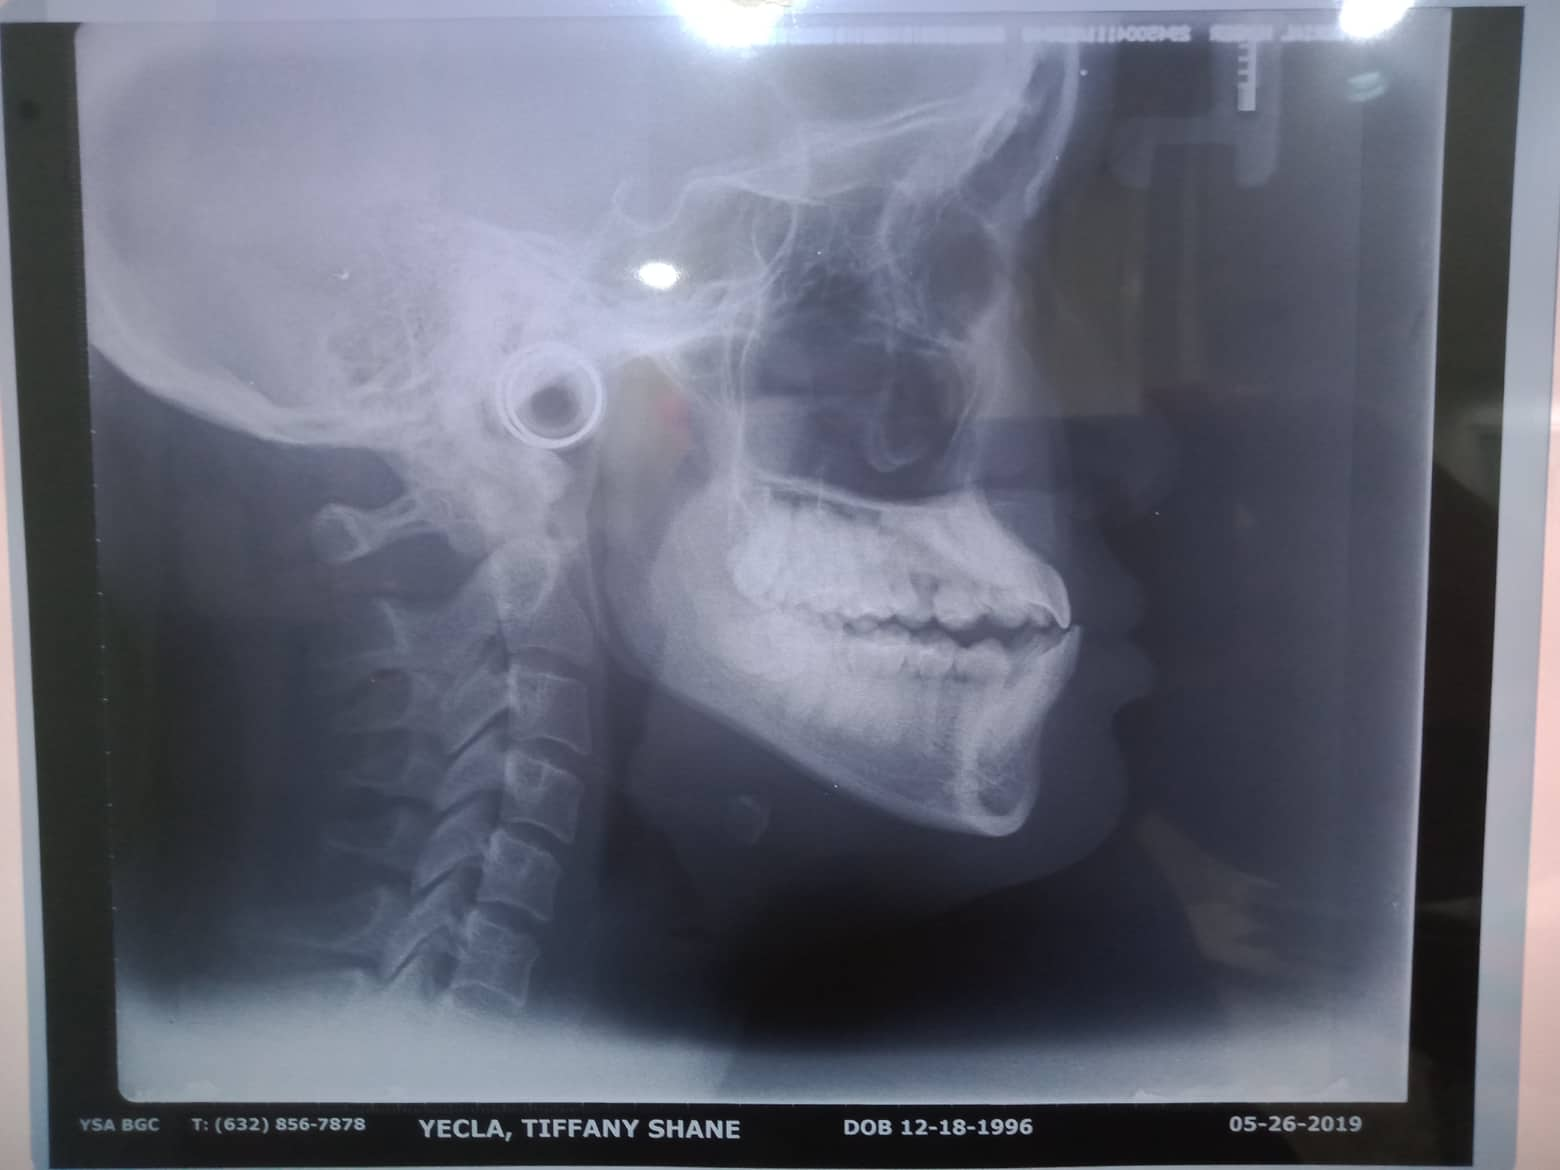

- 08/15/21- adj 16*22UL 18niti 34 09/18/21 - adj. 34^ for removal- for resto 22/34 10/16/21 - REMOVAL OF BRACES RESTO: 17 CAOH occ/14 MO mta/13 LINGUAL DISTAL ESTHETIC 23/22 ALL INCISAL RESHAPING 10/22/21 -lingual retainer up and down wiyh vacuum retainer 3/05/22 LC 14 Mesial + CAOH/ Op 09/08/22 - OP (light) Resto #15 05/13/23- OP(L) For resto #46 06/14/25 OP mild LC #25 fiber, CaoH,ozone,xray 05/21/26 OP